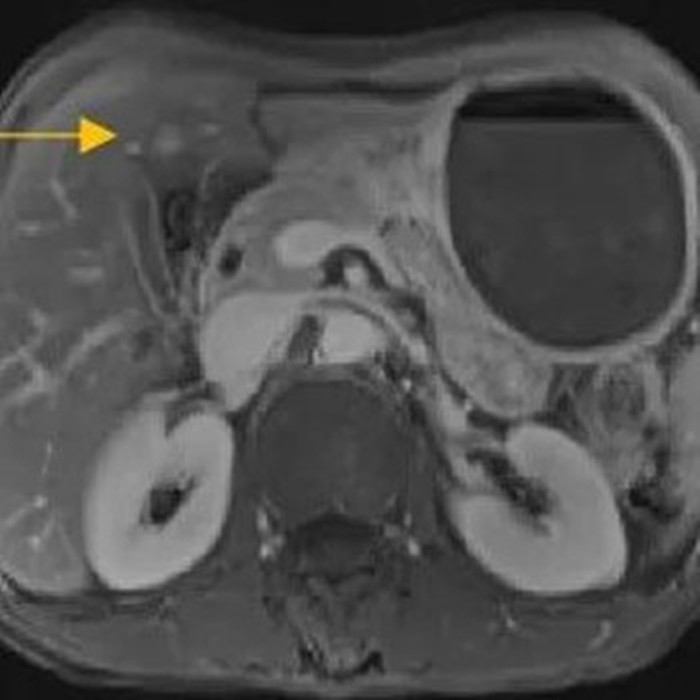

經(jīng)過6個周期,前后4個月的治療,周先生再次復(fù)查CT,提示胃部腫瘤,轉(zhuǎn)移的胃旁淋巴結(jié)、肝臟腫瘤都有明顯縮小,營養(yǎng)狀況良好,能正常進(jìn)食,體重增加了6斤,精神狀態(tài)比原先好了很多。

治療后